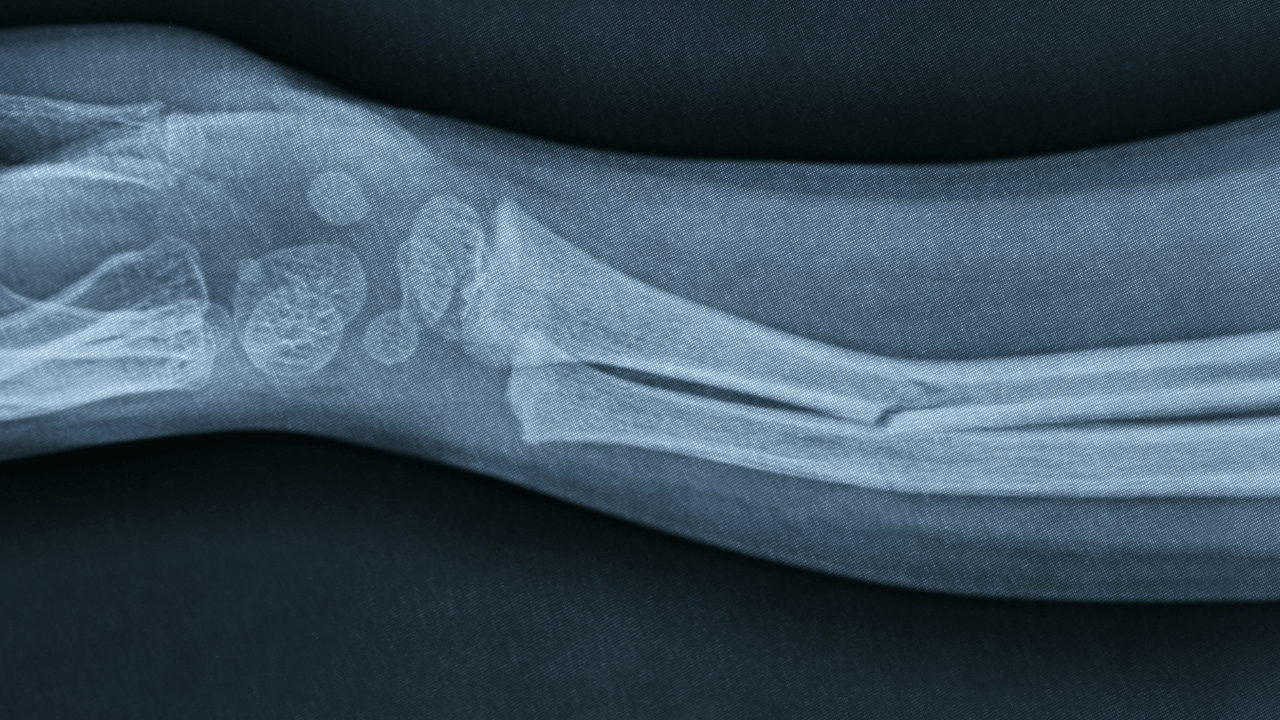

9 Eylül 2025’te düzenlenen basın toplantısında ekip, “Bone-02” adlı kemik yapıştırıcısının klinik araştırma bulgularını kamuoyuna paylaştı. Yerel bilim-teknoloji kaynaklarına göre yapıştırıcı, kanla ıslak fizyolojik ortamda bile 2–3 dakikada güçlü tutunma sağlıyor; laboratuvar testlerinde 400+ jin (yaklaşık 200+ kg) çekme kuvvetine dayanan bağlanma, ~0,5 MPa kesme ve ~10 MPa basma dayanımı raporlandı. Malzeme biyobozunur; kemik iyileşmesiyle birlikte yaklaşık 6 ayda doğal olarak emiliyor.

Parçalı (komminüte) kırıklarda çok sayıda minik kemik parçasını anatomik olarak hizalayıp sabitlemek zor; klasik metal implantlar bu mikrof ragmentleri zahmetli ve kimi zaman yetersiz biçimde tutar. Hızlı yapışan, ıslak-kanlı ortamda çalışan, sonradan vücutta eriyen bir yapıştırıcı; operasyon süresini ve ikincil çıkarma ameliyatlarını azaltma, enfeksiyon ve yumuşak doku hasarı riskini düşürme potansiyeli taşır.